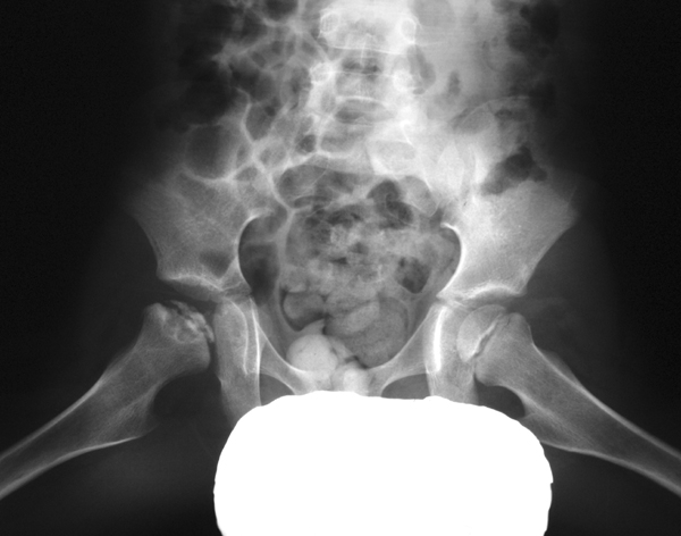

What is the hallmark radiographic sign of hip ischemic necrosis?

Crescent sign – subcortical radiolucent band representing a fracture line.

What does the Crescent sign indicate in avascular necrosis of the femoral head?

A crescent-shaped lucent subchondral fissure indicating a fracture line; seen best in abducted position.